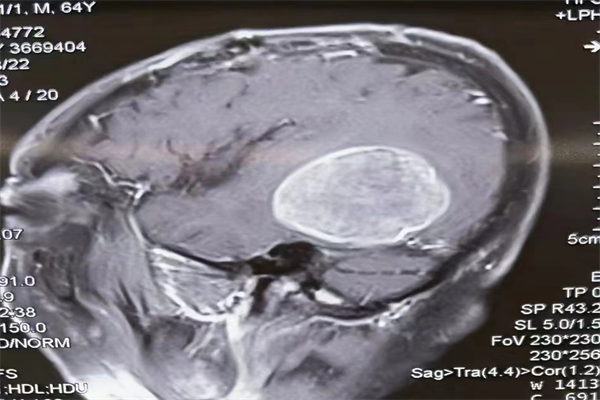

8月初,李叔再次出現(xiàn)頭痛及癲癇等癥狀,得知陳博副院長(zhǎng)在灃東院區(qū)接診,李叔及家人立即從綏德縣來(lái)到灃東院區(qū)神經(jīng)外科門診進(jìn)行復(fù)查。檢查后發(fā)現(xiàn),李叔原有部位腫瘤完全切除,右側(cè)顳葉新發(fā)轉(zhuǎn)移,腫瘤大且位于功能區(qū)。

8月29日上午8時(shí),由陳博副院長(zhǎng)主刀,帶領(lǐng)腦病病區(qū)(神經(jīng)外科)車海江副主任和張海平主治醫(yī)生共同為李叔行幕上開顱腫瘤切除術(shù),手術(shù)歷時(shí)三個(gè)多小時(shí)順利完成,顯微鏡下全切腫瘤。術(shù)后第二天,李叔神志清楚,言語(yǔ)流利,查體合作,無(wú)神經(jīng)功能障礙。